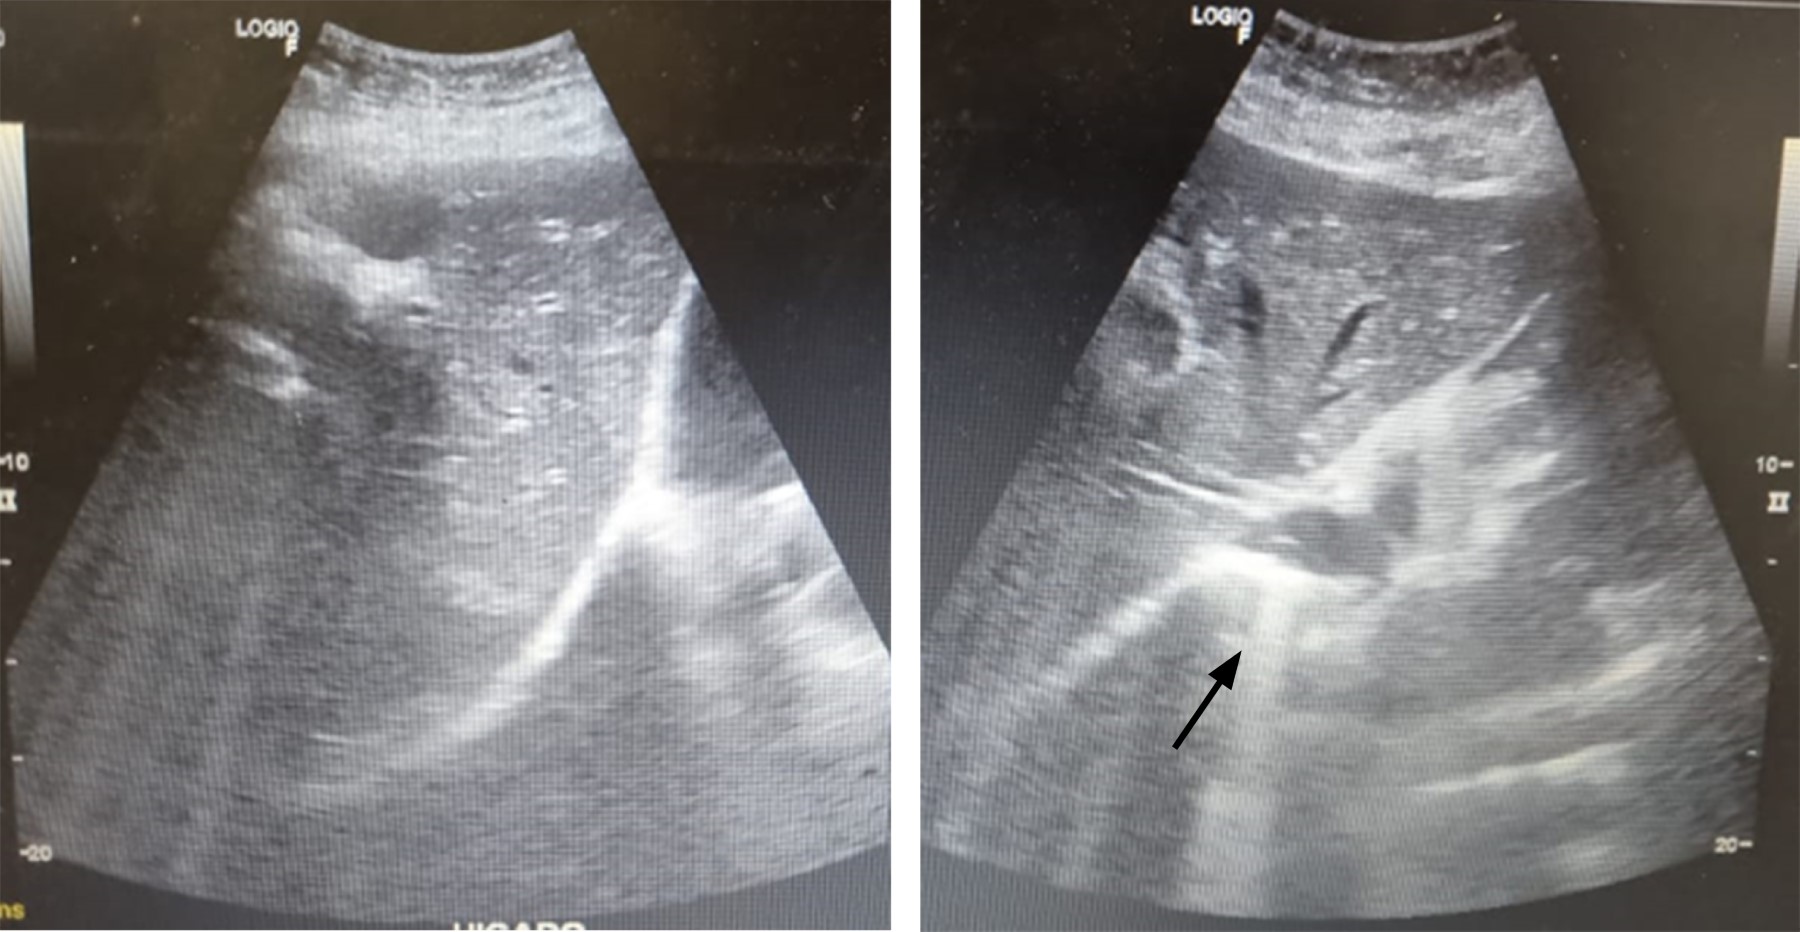

Se trata de paciente femenino de 59 años, que cuenta con antecedente de diabetes mellitus tipo 2 de larga evolución. Acude al servicio de urgencias por presentar dolor de tipo cólico en hipocondrio derecho de seis meses de evolución, de intensidad 6/10 en la escala análoga visual, sin irradiaciones, asociado a la ingesta de alimentos colecistoquinéticos, sin atenuantes, niega fiebre, ictericia, coluria o acolia. A la exploración física, con dolor a la palpación profunda en hipocondrio derecho, Murphy ausente, sin datos de irritación peritoneal. Cuenta con los siguientes laboratorios: hemoglobina 12.9 g/dl, hematocrito 37%, leucocitos 9.4 × 103/μl, plaquetas 360 × 103/μl, glucosa 178 mg/dl, creatinina 0.7 mg/dl, sodio 145 mEq/l, potasio 3.7 mEq/l, cloro 105 mEq/l, bilirrubina total 0.7 mg/dl, fosfatasa alcalina 55 U/l. Se realiza ultrasonido de hígado y vías biliares, el cual revela vesícula biliar con aumento de su ecogenicidad en toda su extensión, provocando fenómeno Wall-Echo-Shadow (WES) con dimensiones de 52.7 × 29.4 × 18.7 mm. Con pared no valorable, colédoco de 5.8 mm, sin evidencia de litos en su interior (Figura 1). Se realiza rastreo tomográfico donde se observa vesícula con volumen de 13.2 cm3, heterogénea, con presencia de densidad aire, pared engrosada de manera regular con presencia de calcificaciones, estómago distendido, con presencia de imagen hiperdensa en su interior (probable lito) (Figura 2).

Figura 1